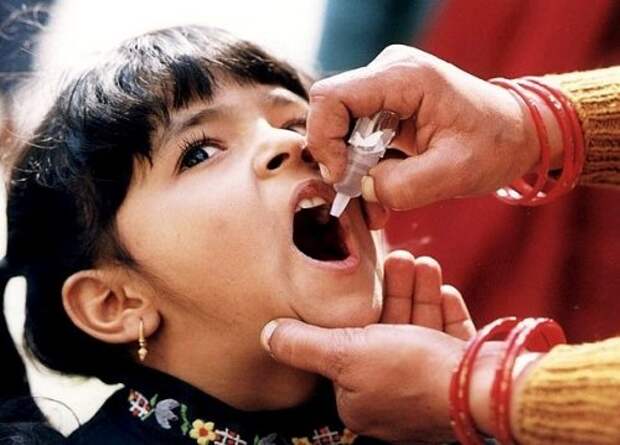

1. Вакцина от полиомиелита

Фото: GDC Global / flickr

26 марта 1953 года американский медицинский исследователь Йонас Солк (Jonas Salk) объявил, что ему удалось провести успешные испытания вакцины против полиомиелита, вируса, который вызывает тяжелое хроническое заболевание. В 1952 году из-за эпидемии этого недуга диагноз был поставлен 58 000 жителей США, и болезнь унесла 3 000 невинных жизней. Это подстегнуло Солка на поиски спасения, и теперь цивилизованный мир в безопасности хотя бы от этой беды.